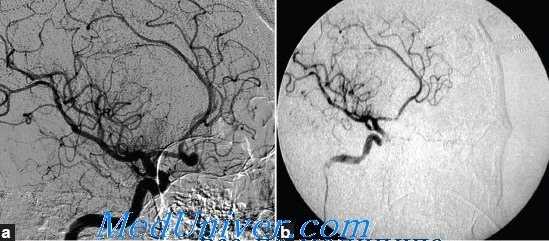

2. Локализация аневризмы. По нашим данным и результатам большинства других исследователей, среди аневризм переднего отдела артериального круга большого мозга наибольшему риску интраоперационного разрыва аневризмы подвержены аневризмы ПСА, а среди аневризм вертебробазилярного бассейна — аневризмы ЗНМА. Частота интраоперационного разрыва аневризмы ПСА достигает 23-40%.

Очевидно, наиболее частое возникновение интраоперационного разрыва аневризмы ПСА обусловлено трудностями диссекции аневризмы, расположенной глубоко в межполушарной щели, вариабельностью расположения шейки и купола аневризмы, особенностями ангиоархитектоники комплекса ПМА-ПСА, увеличивающими гемодинамическую нагрузку на стенки аневризмы. О последнем свидетельствуют следующие факты:

— аневризмы ПСА встречаются наиболее часто (A. Molyneux et al., A. L. Jr. Rhoton, J. Hernesniemi et al.);

— размер разорвавшихся аневризм ПСА меньше аневризмы иной локализации и составляет в среднем 7 мм (J. Hernesniemi et al., Y.G. Jeong et al.);

— риск разрыва аневризмы ПСА вне операции в два раза выше, чем риск разрыва аневризмы другой локализации (J.M. Mira et al., 2006 г.).